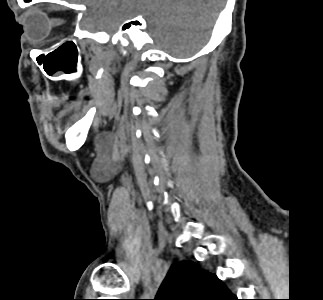

Используемые в нашей клинике томографы, благодаря своему оснащению, позволяют получать снимки высокого качества и детализации за короткий промежуток времени, что минимизирует уровень лучевой нагрузки на организм. Используя полученные данные, аппараты создают трехмерные реконструкции анатомической зоны. Это дает возможность наглядно оценить пространственное соотношение лимфатических узлов и близлежащих органов, выявить прорастание в окружающие ткани, особенно при образовании цепочек, пакетов и конгломератов лимфоузлов.

Для повышения качества визуализации лимфоузлов, особенно при подозрении на онкологических процесс, исследование проводится с внутривенным болюсным контрастированием. Контрастный препарат, содержащий йод, вводится в вену с помощью автоматического шприца. Распространяясь по сосудистой системе, препарат накапливается в патологических очагах, в том числе, в измененных лимфоузлах, и увеличивает их яркость на КТ-изображениях. Методика контрастирования помогает выявлять опухоли минимальных размеров, проводить дифференциальную диагностику между доброкачественными и злокачественными новообразованиями и воспалительными изменениями.

Мультиспиральная КТ позволяет оценить размеры лимфатических узлов, выявить деформацию их контуров, неоднородность структуры, установить точную локализацию, взаимодействие с близлежащими органами и окружающими тканями, обнаружить инфильтрацию прилегающих структур.